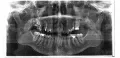

Удалили два зуба. Один - треснул корень, второй - зуб мудрости. Удаляли долго - 1,5 часа. Наложили швы. Укололи укол кеторол напоследок. Прописали азитромицин, нимесил и линекс, хлоргексидин 0,5. Весь день ничего не тревожило. На ночь выпила азитромицин и нимесил с линекс, и пополоскала хлоргексидин 0,5. Утром щека теплая, пока не горит и покраснело то место, где удаляли (скула).